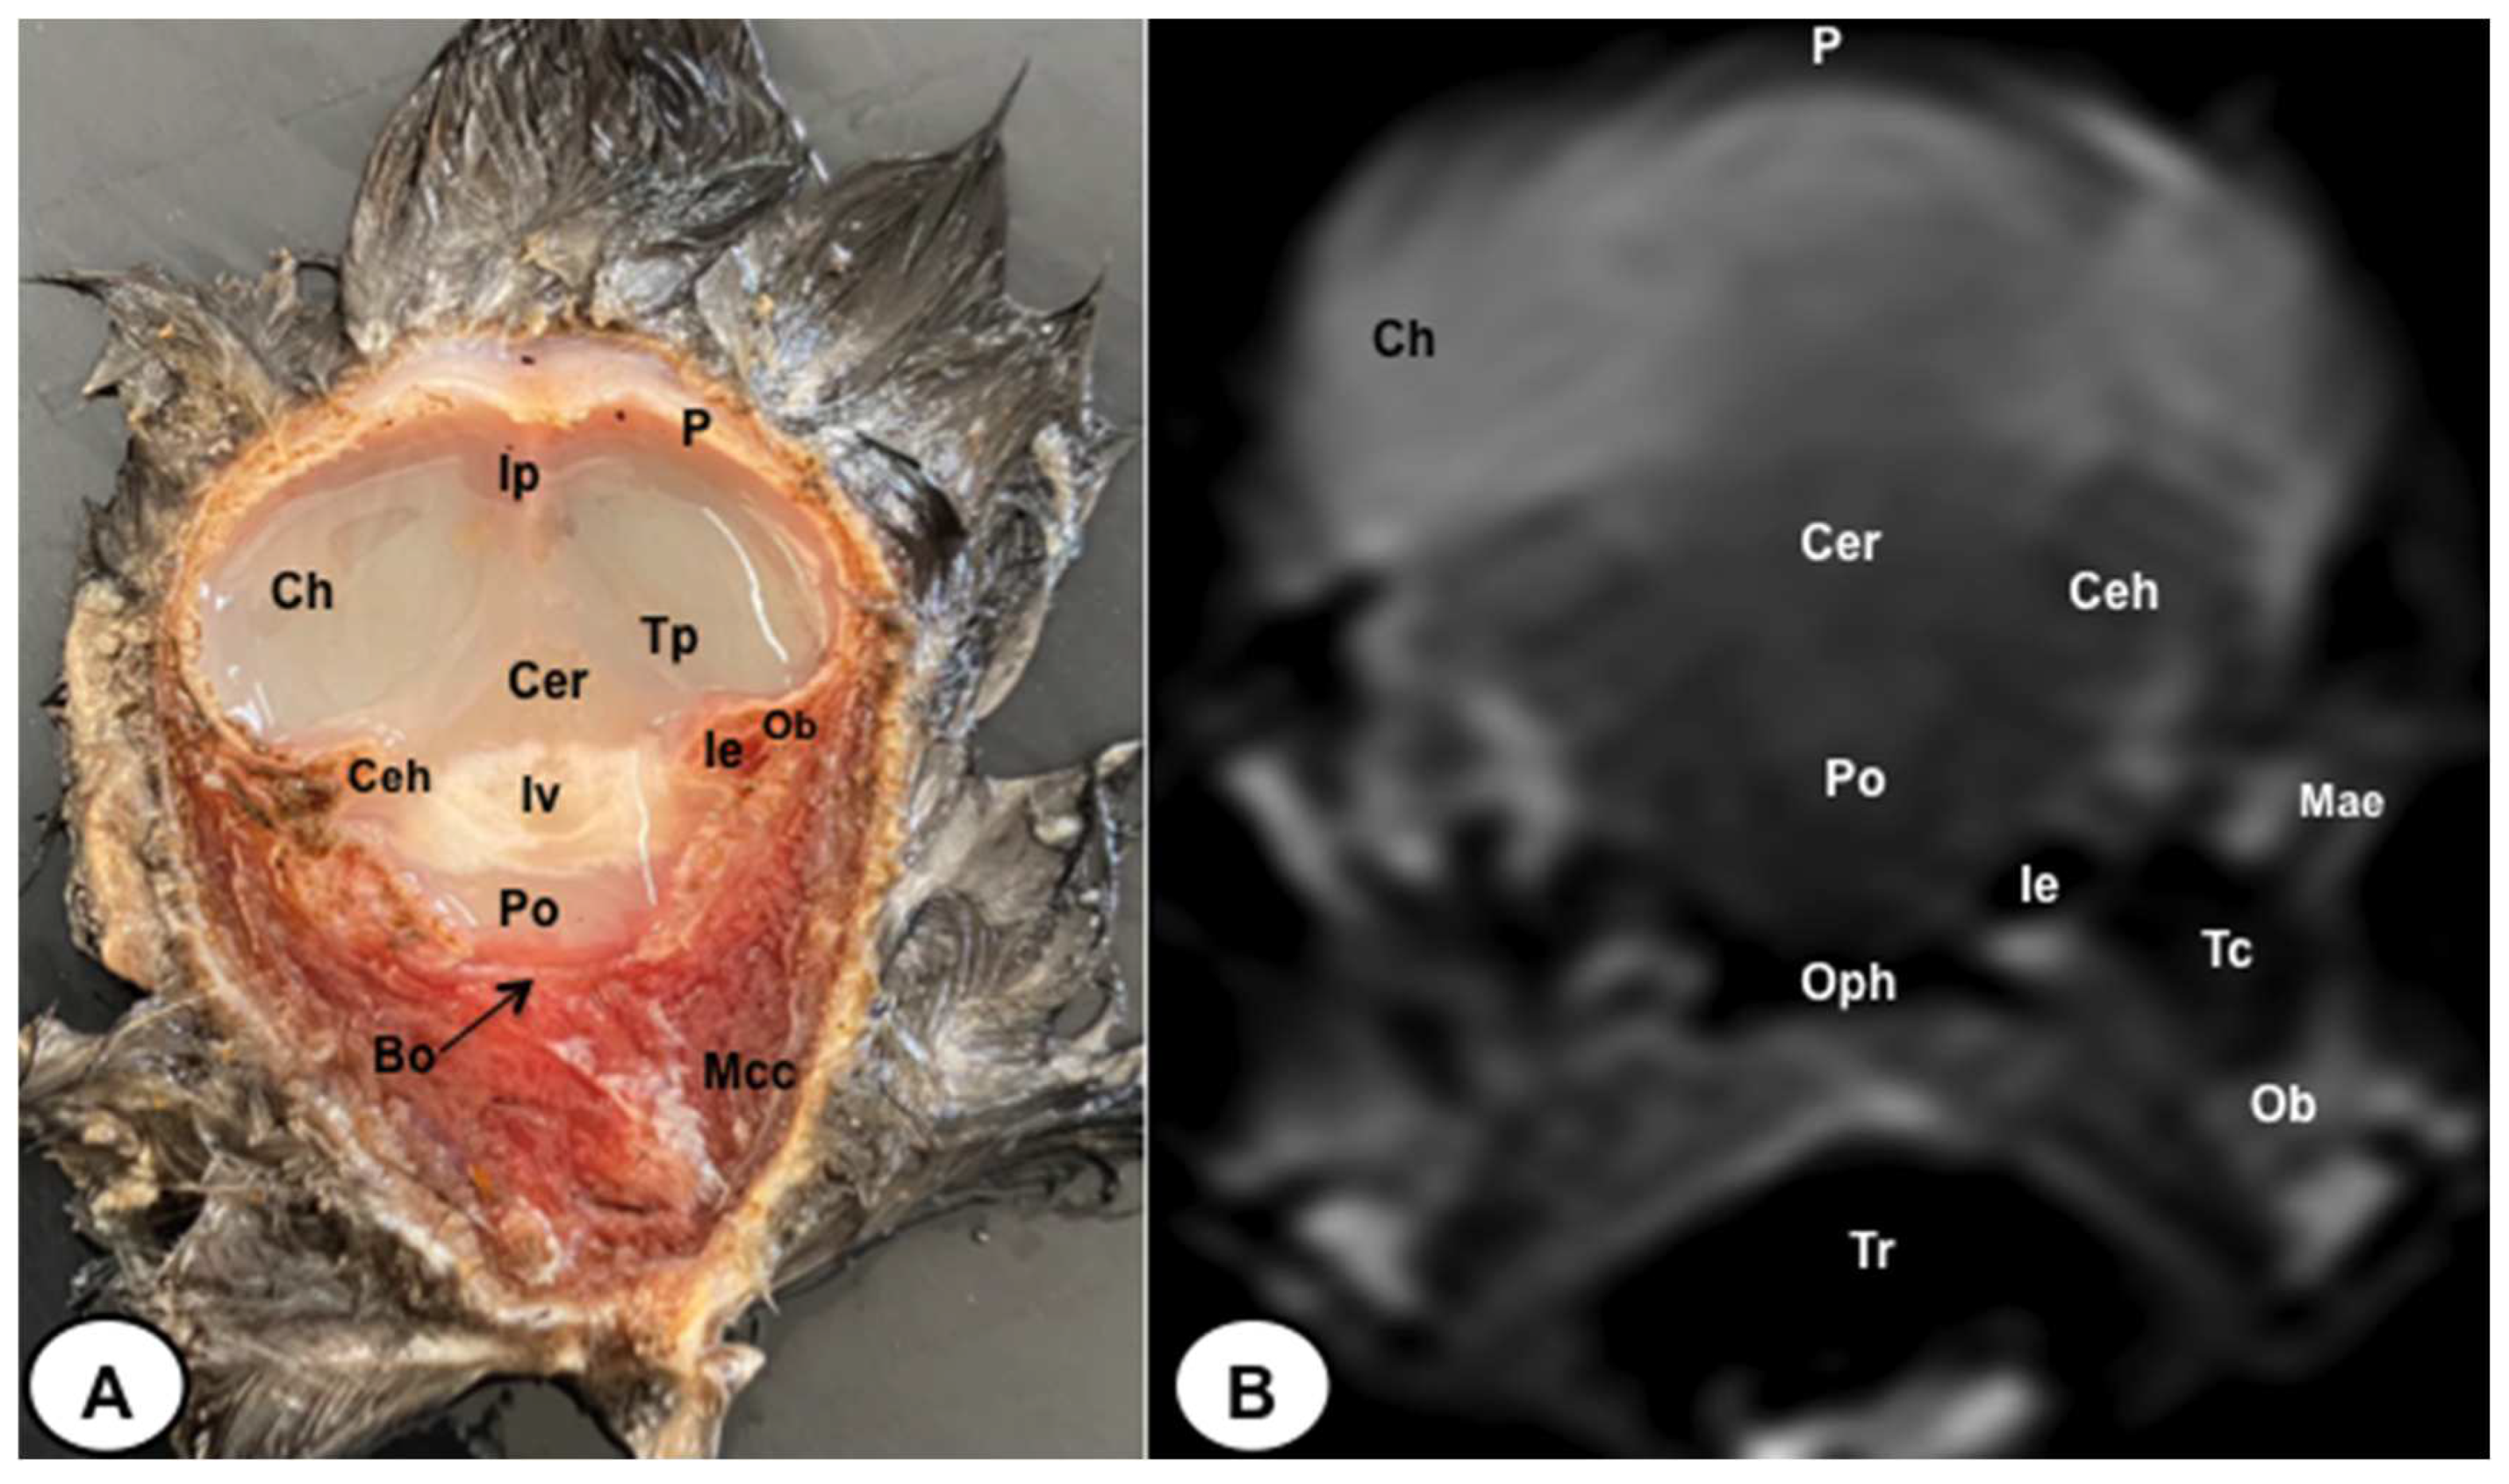

Figure 5. Transverse cross-section (A) and T2W MR (B) images of the atlantic puffin head at the level of the pons corresponding to line IV inFigure 1. P: Os parietale; Ip: interparietal bone; Tp: tentorial process; Bo: Os basioccipitale; Ob: otic bones; Ch: cerebral hemisphere; Ceh: cerebellar hemisphere; Cer: cerebellum (body); IV: fourth ventricle; Po: pons; Mae: Meatus acusticus externus; Ie: inner ear; Mcc: Musculus cucularis capitis; Oph: oropharynx; Tr: trachea.

The anatomical sections presented in this study were quite helpful in identifying different structures belonging to the central nervous system and its associated structures, which were labelled following the Nomina Anatomica Avium. Therefore, we observed the avian brain with the telencephalic hemispheres containing the lateral ventricles (see Figure 4A and Figure 7A). Both hemispheres were separated by the fissura longitudinalis cerebri (Figure 6A and Figure 7A). In addition, transverse cross sections were quite helpful in distinguishing a slightly caudolateral disposed rostral groove, the vallecula telencephali, which was presented on the dorsal surface of each hemisphere, as well as a little pointed olfactory bulb situated at the rostral end of each hemisphere (see Figure 2A, Figure 3A and Figure 7A). The diencephalon was identified as a rostral continuation to the mesencephalon and represents the rostral limit of the brain stem (Figure 10A). The dorsal and sagittal anatomical sections allowed the visualisation of some components of the hypothalamus, such as the optic chiasm and the optic nerve penetrating the sclera (see Figures 8A–10A). Besides, these sections allowed us the identification of other components of the Atlantic puffin brain, such as the dorsal part of the mesencephalon, as well as the large unpaired median corpus cerebelli, the internal medullary body with an internal white substance and the little paired cerebellar hemispheres (Figures 4A, 5A, 6A, 7A 8A, 9A and 10A). Moreover, these sections allowed the identification of the ventral part of the rhombencephalon, including the pons and the medulla oblongata, which did not present an obvious demarcation (see Figures 4A, 5A, 6A, 7A, 8A, 9A and 10A).

No discernible anatomical distinctions were evident in the examined juvenile puffins. T2-weighted magnetic resonance (T2W MR) images demonstrated a precise alignment with the cranial structures observed in the cadaveric cross sections, furnishing comprehensive insights into the central nervous system (CNS) and its associated structures. Consequently, various constituents of the puffin head’s CNS, the bulbus oculi, and their related elements were adequately differentiated. Thus, in the transverse and dorsal planes, the two telencephalic hemispheres were homogeneous, displaying regions of moderate and hypointense signals corresponding to the cerebral hemispheres and lateral ventricles, respectively (see Figures 3B, 4B, 5B, 6B, 7B and 10B). Notably, these two planes facilitated the identification of the olfactory bulb, which was a small rostrally tapering structure with moderate and homogeneous signal intensity (see Figures 2B, 3B and 7B). The hyperpallium, distinguished by its curved dorsal contour and moderate signal intensity, was another distinct structure identified (see Figure 3B). Conversely, the diencephalon, another forebrain component, displayed limited differentiation from the adjacent mesencephalon, manifesting moderate to low-intensity signals (see Figure 10B). Additionally, prominent features of the mesencephalon, such as the optic lobe, were exclusively discerned in the dorsal T2W MR images, showcasing analogous signal characteristics (see Figures 4B, 8B and 9B). Other essential components of the CNS, including the pons, and the medulla oblongata, were identifiable in the transverse, dorsal and sagittal planes, characterized by low-intensity signals (see Figures 4B, 5B, 6B, 8B, 9B and 10B). Adjacent to the brain stem, the corpus cerebelli and the small paired cerebellar hemispheres exhibited poorly defined regions of hypo-and moderate intense signal (see Figures 4B, 5B, 6B, 7B, 8B, 9B and 10B).

Similar to terrestrial mammals, the cerebellum of the Atlantic puffin lies above the midsection of the mesencephalon, the pons, and the medulla oblongata, with no discernible clear demarcations between these regions. Examination through transverse cross-sections and T2-weighted MR images revealed the presence of two small cerebellar hemispheres and a larger unpaired central structure. These cerebellar structures were separated by transverse fissures, facilitating a distinct separation between them. Furthermore, these fissures exhibited a marked differentiation between the gray and white matter within the cerebellum.